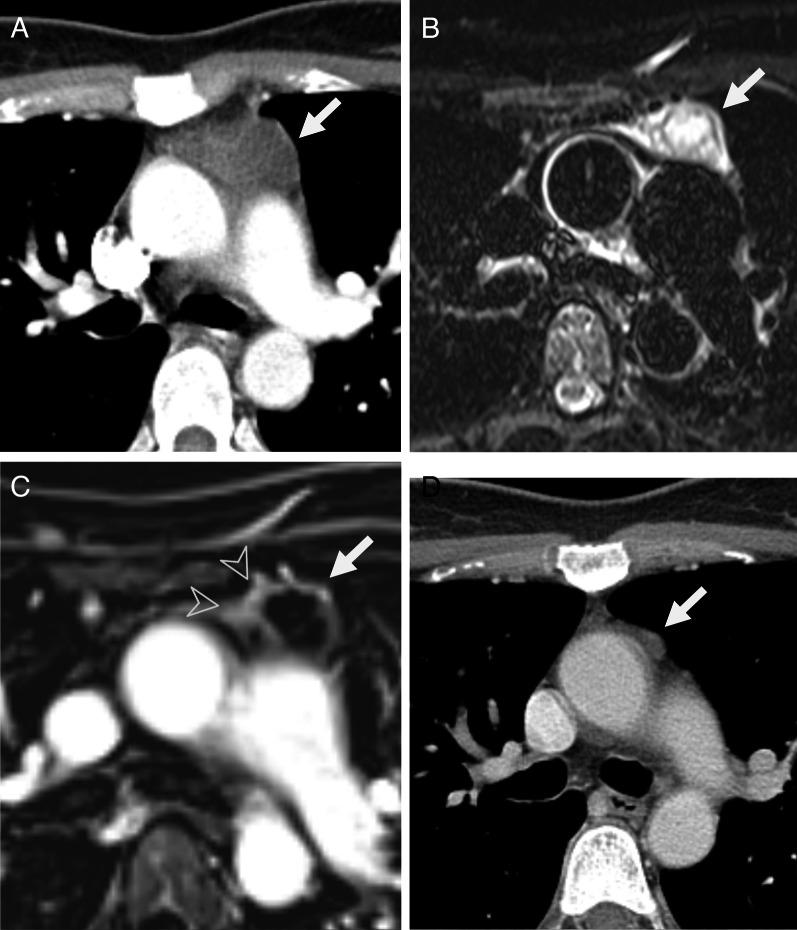

In this multicenter retrospective study, patients who underwent contrast-enhanced chest MRI in two tertiary centers to assess anterior mediastinal cystic lesions were included after excluding overt solid tumors and thymic hyperplasia. Anterior mediastinal cystic lesions were classified into two categories: probable (simple) cyst or indeterminate lesion (complex cyst). Size and imaging features of lesions during follow-up were evaluated and clinical outcomes were assessed.

A total of 204 patients (mean age, 59 ± 11 years; M:F = 111:93) were studied; 186 (91.2%) were classified as probable cysts and 18 (8.8%) as indeterminate lesions on MRI. Among patients with probable cysts and more than 2 years of follow-up, lesion size was unchanged in 39.6% (36/91), decreased in 16.5% (15/91), and fluctuated in 8.8% (8/91). All patients who underwent surgery were confirmed cysts. None developed mural nodules or irregular wall thickening, suspicious for malignancy during follow-up. In patients with indeterminate lesions, 16.7% (3/18) had pathologically confirmed thymoma and 44.4% (8/18) had proven cysts. Follow-up numbers and intervals after MRI in patients with probable cysts were variable among physicians and institutions in clinical practice (p < 0.05) but more than half were followed for up to 2 years in two centers.